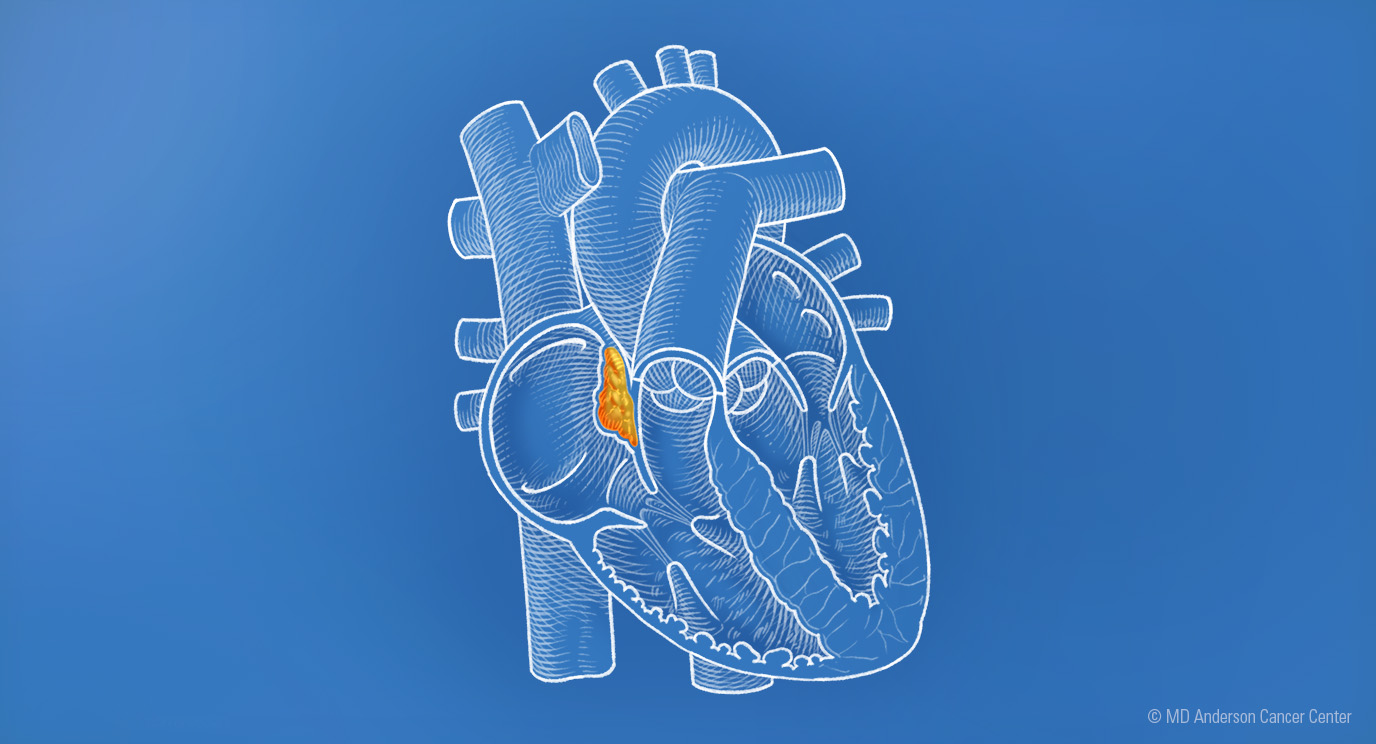

Heart cancer: Insights on diagnosis, treatment and research